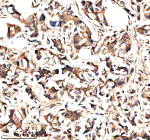

IHC analysis of NEK9 using anti-NEK9 antibody. NEK9 was detected in a paraffin-embedded section of human breast cancer tissue. Heat mediated antigen retrieval was performed in EDTA buffer (pH 8.0, epitope retrieval solution). The tissue section was blocked with 10% goat serum. The tissue section was then incubated with 2 ug/ml rabbit anti-NEK9 antibody overnight at 4oC. Peroxidase Conjugated Goat Anti-rabbit IgG was used as secondary antibody and incubated for 30 minutes at 37oC. The tissue section was developed using an HRP secondary and DAB substrate.